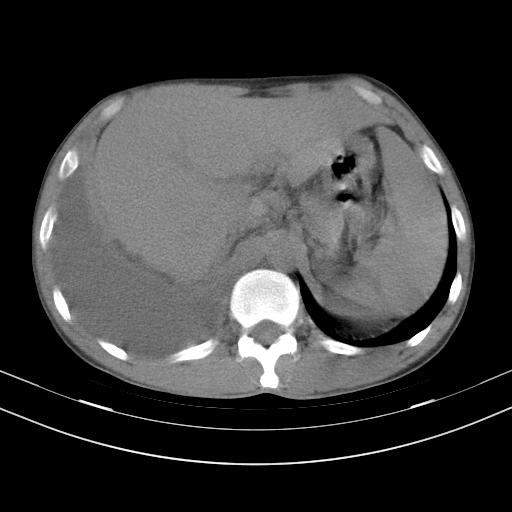

男性,44岁,结核病史多年。现胸闷气短,咳嗽,偶咳血。

双肺多发结节影最分空洞形成考虑占位不除外结核

1、右侧大量胸腔积液伴右肺压缩性膨胀不全,建议抽液治疗后复查 2、两肺继发性tb伴空洞形成。

1)两肺继发性肺结核伴空洞形成,左肺多发性结核球。2)右侧大量胸腔积液伴右肺部分膨胀不全。3)纵隔淋巴结肿大。

吉大一院胸水抽检结果:结核性胸水